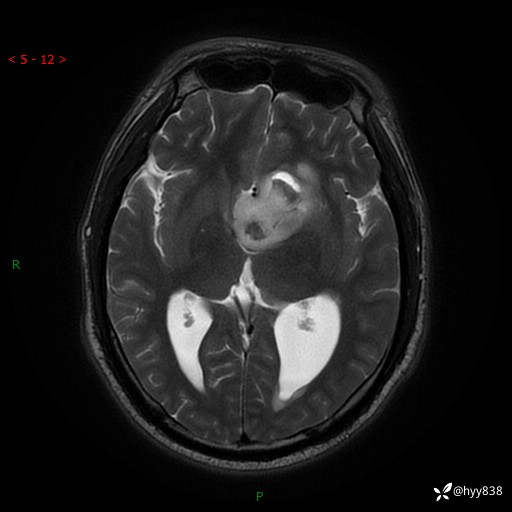

颅脑MRI平扫+增强